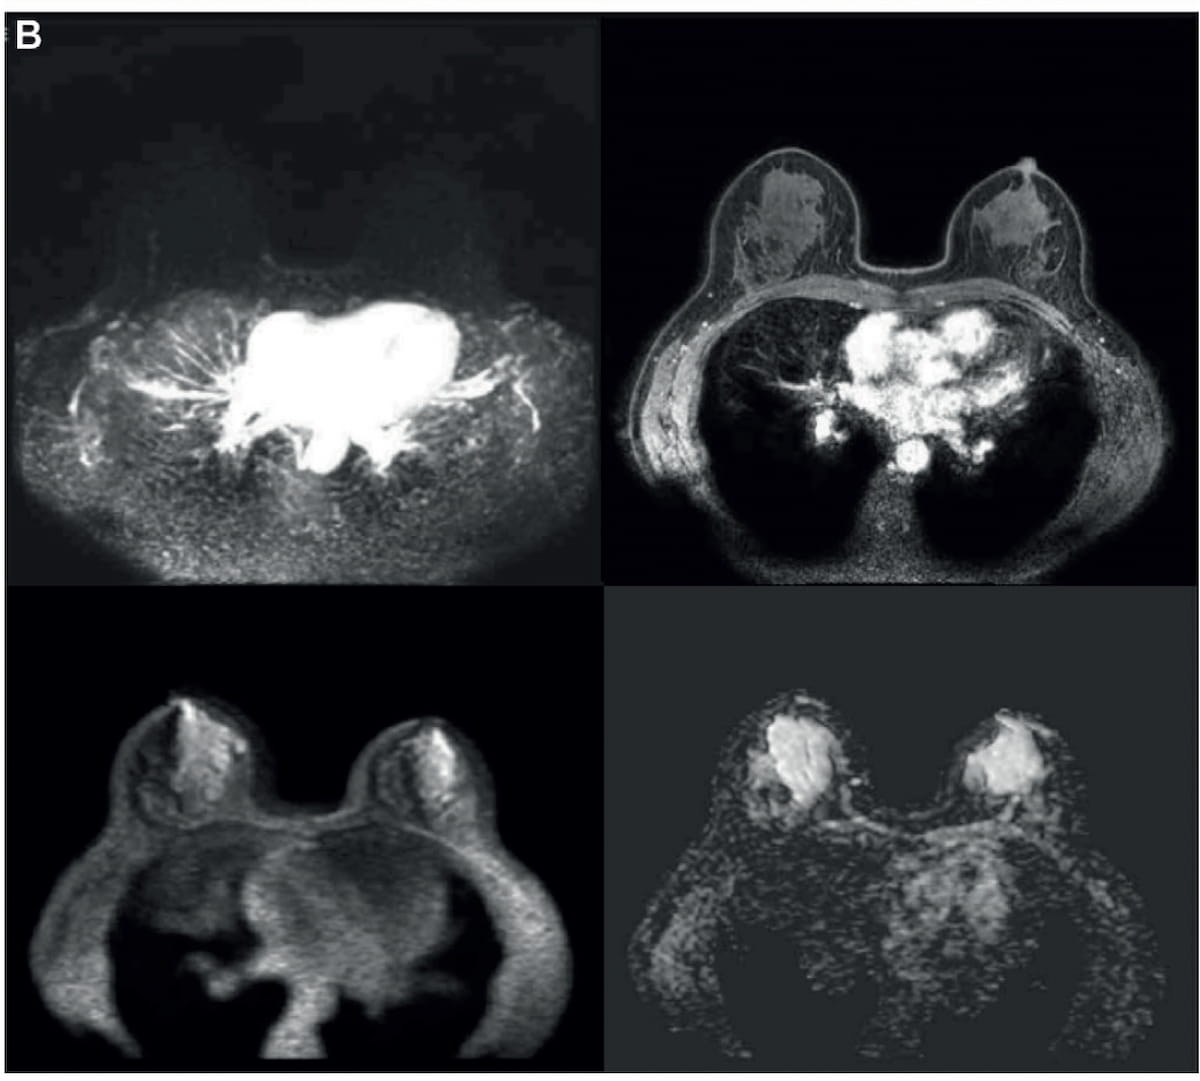

Study: Abbreviated Breast MRI Offers Equivalent Accuracy to mpMRI for Women with Dense Breasts

For women with extremely dense breasts, new research suggests that abbreviated breast magnetic resonance imaging (MRI) facilitates significant reductions in scanning and reading time in comparison to multiparametric MRI (mpMRI) without sacrificing accuracy …